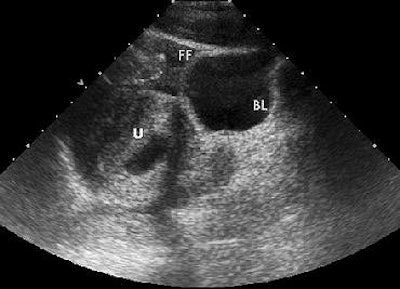

| Above, axial control sonogram obtained at level of injury does not show any parenchymal abnormality. Below, axial contrast-enhanced sonogram reveals liver injury as deep hypoechoic area (between arrows) surrounded by enhanced hyperechoic parenchyma. |

| Poletti PA, Platon A, Becker CD, Mentha G, Vermeulen B, Ubhler LH, Terrier F, "Blunt Abdominal Trauma: Does the Use of a Second-Generation Sonographic Contrast Agent Help to Detect Solid Organ Injuries?" (AJR 2004; 183:1293-1301). |